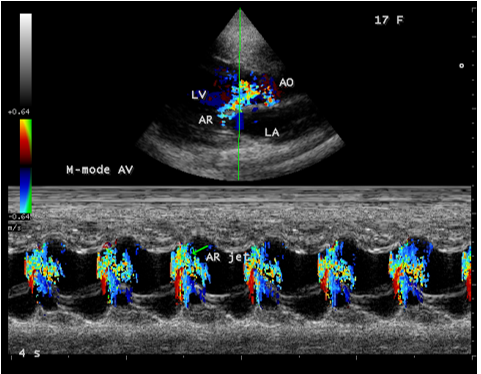

Figure 11: Color M-mode (green line) showing the acute severe aortic regurgitation (arrow-AR jet) in a 17-year old female.

Figure 12: Apical view showing the dilated left ventricle and a normal left atrium in a 17-year old female in acute severe aortic regurgitation.

Since the patient had a bicuspid aortic valve as shown in Figure 9 and a history of rheumatic fever during childhood, rheumatic inflammation occurred on the aortic valve and harboured the infective vegetation through the vascular access during the treatment of febrile episodes. Patients with infective endocarditis are at risk of developing acute aortic regurgitation and the ECG can appear normal as in Figure 1 and the chest X-ray usually shows pulmonary edema with normal heart size. A dilated left ventricular cavity with a normal left atrium as in Figure 12 indicates that the volume overload on the left ventricle resulted a compensatory mechanism to maintain an adequate forward stroke volume by accomodating a large regurgitant fraction without an increase in end-diastolic pressure. The heart rate appeared normal (87 bpm) as the result of this compensation. Even though the aortic regurgitation is acute as in Figure 10 which showed a steep deceleration slope with a narrow width of regurgitant jet due to endocarditic lesion of aortic valve (endocarditic regurgitation). It is compensated in this patient and showed a lesser degree of decompensation as moderate LV dysfunction with an ejection fraction of 42% as in Figure 13, necessitating elective aortic valve replacement along with removal of vegetations with a mechanical prosthetic valve. Anticoagulation with warfarin to maintain the INR (international normailised ratio) between 2 to 3 is indicated after the clearance of active stage of endocarditis with antibiotic therapy and surgery.